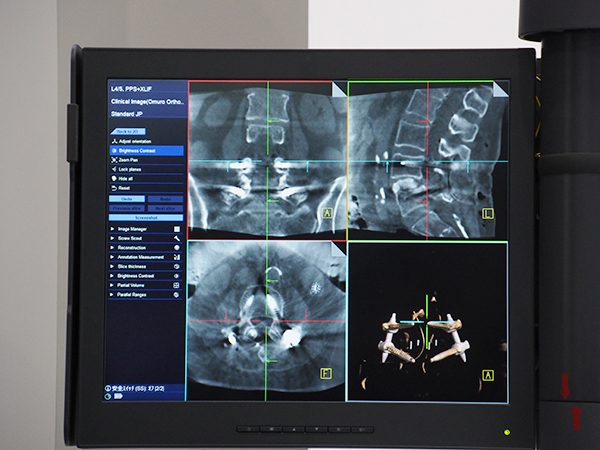

FPD搭載のCアームシステムCios Spinは,開口径がクラス最大級の93.6cmあり,ベッドの配置や患者の体格で制限を受けにくく,使いやすさが特長となっている。Cアームのデザインはアイソセントリック機構を採用しているため,患者に対してCアームを適正な位置にポジショニングした後は,Cアームを正面や側面に動かしても常に患者を中心に回転することが可能で,位置調整をする必要がない。また,Cアームにも操作パネルを搭載し,術者側でも操作することができる。高解像度コーンビームCT “Retina 3D”では,Cアームを約200°回転させて100〜400の投影データを収集,再構成した3D画像をモニタ上に表示する。3D画像上では,スクリュー自動検出機能“Screw Scout”(オプション)により自動的にスクリューを認識・検出でき,3D撮影後すぐにスクリュー位置の評価が可能で術者は手技に集中することができる。脊椎領域で高い評価を得ており,今後はナビゲーションシステムやロボットアームとの連携でさらなる価値の向上をめざすほか,外傷領域や呼吸器領域への提案も強化し,臨床活用の幅を広げていくとしている。

脊椎領域で高い評価を得る外科用X線撮影装置「Cios Spin」

スクリュー自動検出機能“Screw Scout”により,撮影後すぐに3Dでスクリュー位置の確認が可能